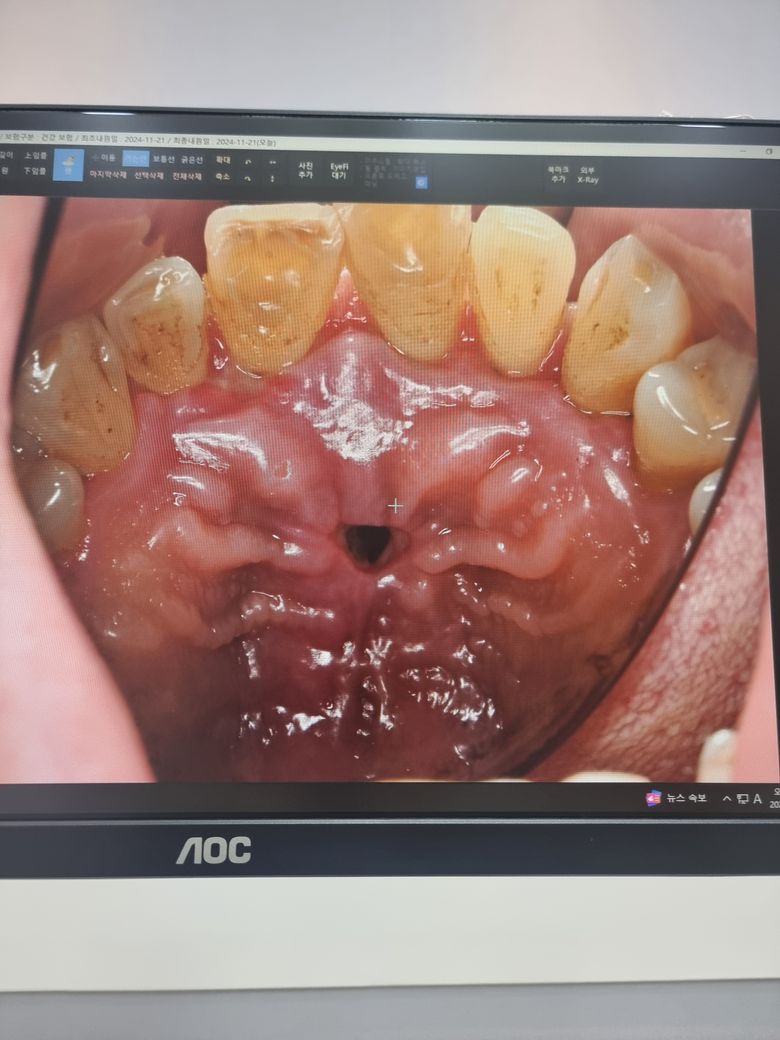

치근단 낭종 제거술후 입천장에 구멍이 생겼어요ㅠㅠ

입천장에 구멍이 났는데 어떻게해야 하나요?

치근단 낭종 제거수술을 받은 후

입천장이 구멍이 났어요.

(사진은 수술후 8일경과시점,실밥제거 직후시점)

• 1번 째 사진

1. 입천장이나 잇몸의 작은 구멍의 경우 자연스럽게 닫히고 금방 회복되기도 합니다.

2. 다만 사진 정도의 사이즈라면 대학병원 가서 추가적인 처치를 받는 것을 권고드립니다.